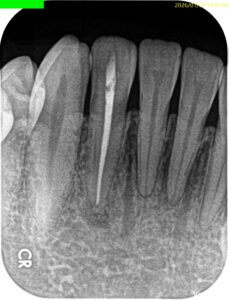

#26 RCT 9M recall(2026.1.7)

初診時と比較した。

問題が縮小していることがわかる。

が、消失ではないのでまた半年後に見せてもらうことになった。